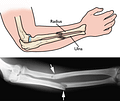

ulna

Xương trụ là một trong hai xương dài của cẳng tay, có dạng hình lăng trụ. Theo vị trí giải phẫu xương trụ nằm về phía trong của cẳng tay gần cơ thể, song song với xương quay ở cả hai tay, gồm 1 thân, 2 đầu.